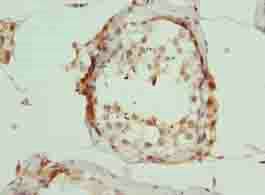

IHC (Immunohiostchemistry)

(Immunohistochemistry of paraffin-embedded human testis tissue using AAA229489 at dilution of 1:100)